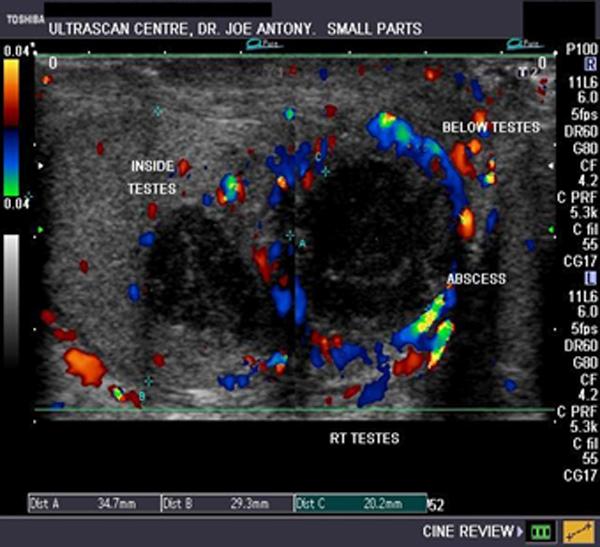

fever

scrotal pain

swelling

untreated orchitis

Testicular abscess